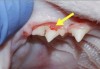

Tooth Resorption in Cats

Tooth resorption represents one of the most common diseases seen in domestic cats and occurs in 20-75% of cats depending on the population studied. Older and purebred cats are more likely to be affected and the numbers of teeth that can be affected increases with age. This unusual condition was probably first identified properly in […]